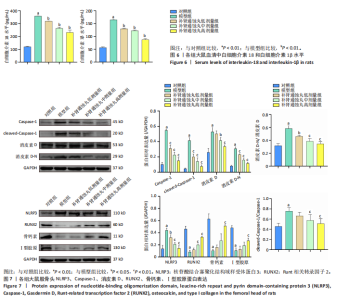

.1 实验动物数量分析 参加实验SD大鼠数量为50只,均进入结果分析。 2.2 Micro-CT检测结果 通过Micro-CT观察各组大鼠股骨头区域骨质变化,见图1。乙醇会导致大鼠股骨头软骨下骨骨量明显减少,骨小梁排列出现紊乱、稀疏等状况,而补肾通蚀丸能够改善上述情况,且呈现一定的剂量效应。模型组骨小梁厚度、骨小梁数目、骨体积分数、骨密度较对照组显著降低(P < 0.01),模型组骨小梁间隙较对照组则显著升高(P < 0.01)。经过不同剂量补肾通蚀丸干预后,各项指标均出现不同程度的逆向改变;其中,与模型组比较,补肾通蚀丸高剂量组骨小梁厚度、骨小梁数目、骨体积分数、骨密度均显著升高(P < 0.05),骨小梁间隙则显著降低(P < 0.05);与模型组比较,补肾通蚀丸中剂量组骨体积分数、骨密度显著升高(P < 0.05),骨小梁间隙则显著降低(P < 0.05);而补肾通蚀丸低剂量组仅在骨小梁间隙指标上较模型组显著降低(P < 0.05),见图2。 2.3 苏木精-伊红染色结果 与对照组比较,模型组大鼠股骨头出现核固缩现象,多见脂肪空泡,部分骨小梁出现断裂、变细;补肾通蚀丸低、中、高剂量组骨细胞核固缩和脂肪空泡较模型组有所减少;在整体结构方面,补肾通蚀丸低剂量组骨小梁变细现象较模型组未见明显改善,但断裂情况有所改善;而补肾通蚀丸中、高剂量组骨小梁断裂、变细情况较模型组均明显改善,见图3;在空骨陷窝率方面,模型组较对照组显著增高(P < 0.01);补肾通蚀丸中、高剂量组较模型组有所降低(P < 0.05),见图3。 2.4 免疫组化染色结果 与对照组比较,模型组NLRP3、Caspase-1、消皮素D蛋白表达明显增强,而Runt相关转录因子2、骨钙素、Ⅰ型胶原蛋白表达显著降低(P < 0.01);与模型组比较,补肾通蚀丸中、高剂量组能够显著降低NLRP3、Caspase-1、消皮素D蛋白表达,且促进Runt相关转录因子2、骨钙素、Ⅰ型胶原蛋白表达(P < 0.05),而补肾通蚀丸低剂量组骨钙素、Ⅰ型胶原蛋白表达有所上调(P < 0.05),其余指标则无明显差异(P > 0.05),见图4,5。 2.5 ELISA检测结果 与对照组比较,模型组大鼠血清中白细胞介素18和白细胞介素1β水平显著增高(P < 0.01);与模型组比较,补肾通蚀丸各剂量组大鼠血清中白细胞介素18和白细胞介素1β水平均显著降低(P < 0.01),且以一定剂量依赖方式递减,见图6。 2.6 Western blot检测结果 与对照组比较,模型组大鼠股骨头组织中NLRP3、cleaved-Caspase-1、Caspase-1、消皮素D、消皮"

素D-N蛋白表达均显著上调(P < 0.01),成骨因子Runt相关转录因子2、骨钙素、Ⅰ型胶原蛋白表达均显著下调(P < 0.05);补肾通蚀丸各剂量组NLRP3、cleaved-Caspase-1、Caspase-1、消皮素D、消皮素D-N蛋白表达以一定剂量依赖方式呈现不同程度的下调,Runt相关转录因子2、骨钙素、Ⅰ型胶原蛋白表达则以一定剂量依赖方式呈现不同程度的上调;与模型组比较,补肾通蚀丸中、高剂量组NLRP3、cleaved-Caspase-1、Caspase-1、消皮素D、消皮素D-N蛋白表达均显著下调(P < 0.05),补肾通蚀丸高剂量组Runt相关转录因子2、骨钙素、Ⅰ型胶原表达均显著上调(P < 0.01),补肾通蚀丸中剂量组Runt相关转录因子2蛋白表达显著上调,而骨钙素、Ⅰ型胶原表达无明显差异(P > 0.05),补肾通蚀丸低剂量组Runt相关转录因子2、骨钙素、Ⅰ型胶原表达均无明显差异(P > 0.05),见图7A,B。与对照组比较,模型组cleaved-Caspase-1/Caspase-1比值和消皮素D-N/消皮素D比值均显著上升(P < 0.01);与模型组比较,补肾通蚀丸中、高剂量组cleaved-Caspase-1/Caspase-1比值和消皮素D-N/消皮素D比值均显著下降(P < 0.01),而补肾通蚀丸低剂量组cleaved-Caspase-1/Caspase-1比值与对照组比较无明显差异(P > 0.05),见图7C。 2.7 RT-qPCR检测结果 RT-qPCR结果显示,与对照组比较,模型组大鼠股骨头组织中NLRP3、Caspase-1、消皮素D mRNA表达显著上调,Runt相关转录因子2、骨钙素、Ⅰ型胶原mRNA表达显著下调(P < 0.01);与模型组比较,补肾通蚀丸中、高剂量组NLRP3、Caspase-1、消皮素D mRNA表达均显著下调,Runt相关转录因子2、骨钙素、Ⅰ型胶原mRNA表达均显著上调(P < 0.01),而补肾通蚀丸低剂量组NLRP3、Caspase-1、Runt相关转录因子2、骨钙素mRNA表达均无明显差异(P > 0.05),见图8。"